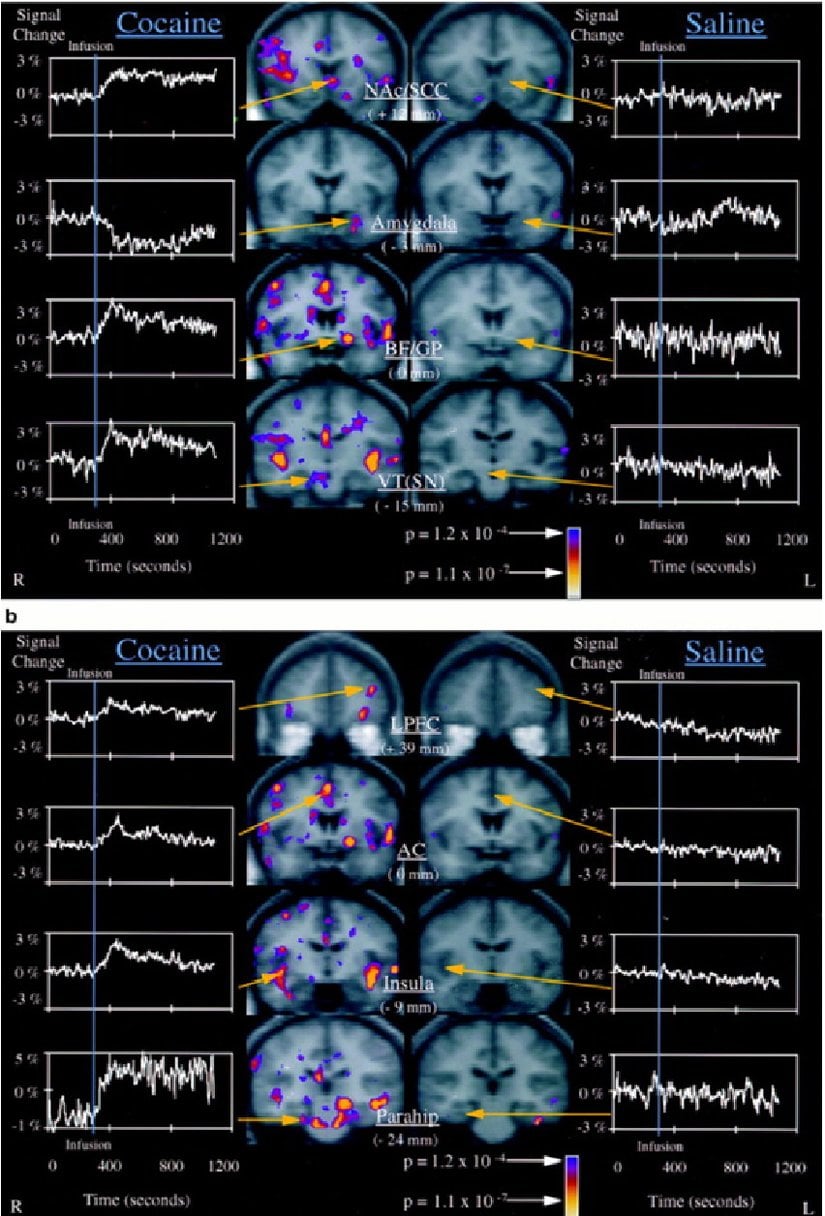

(a) Kokainden sonra önemli fMRI sinyal değişiklikleri gösteren, ancak salininfüzyonlarından sonra olmayan subkortikal beyin bölgelerinin görüntüleri. Solda, kokain alan on denekten ortalama fMRI verileri için infüzyon öncesi ve sonrası zaman noktalarının dört koronal seviyesindeki Kolmogorov-Smirnov (KS) istatistiksel haritaları bulunmaktadır. Bu KS istatistiksel haritaları, karşılık gelen gri tonlamalı ortalama yapısal haritalar üzerinde sözde renkte kaplanmıştır. Pozitif sinyal değişikliği olan aktivasyonlar NAc/SCC, BF/GP ve VT'yi içerirken, negatif sinyal değişikliği olan aktivasyonlar amigdalayı içerir.

(b) Kokain ve salininfüzyonlarından sonra diğer paralimbik ve heteromodal korteks aktivasyonlarının görüntüleri. Gösterilen bölgeler arasında lateralprefrontal korteks (LPFC), anteriorsingulat, insula ve parahipokampalgirus bulunur. Görüntü ve grafik düzeni (a)'da açıklanan kuralları takip eder.

Yukarıdaki özet şemalar, kokain infüzyonundan sonra aktif olacağı tahmin edilen beyin bölgelerinin (sarı renkle işaretli) bir şemasıdır. Başlangıç ve infüzyon sonrası karşılaştırmalarda görülen bir pontin aktivasyonunda potansiyel olarak kapsanan diğer iki beyin sapı monoaminerjik bölgesi de mavi renkle gösterilmiştir.